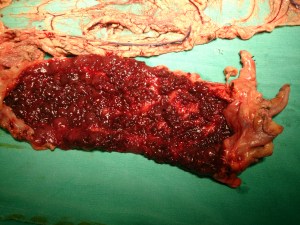

Subtotal colectomy and ileostomy for severe ulcerative colitis (pancolitis). Young (25 years old) patient, with fulminant ulcerative colitis, which had had remissions earlier, but now had actually become more severe, with the patient having developed abdominal pain, as well as increase in the number of bloody stools (now more than 10 per day). Referred from medical ward for surgery.